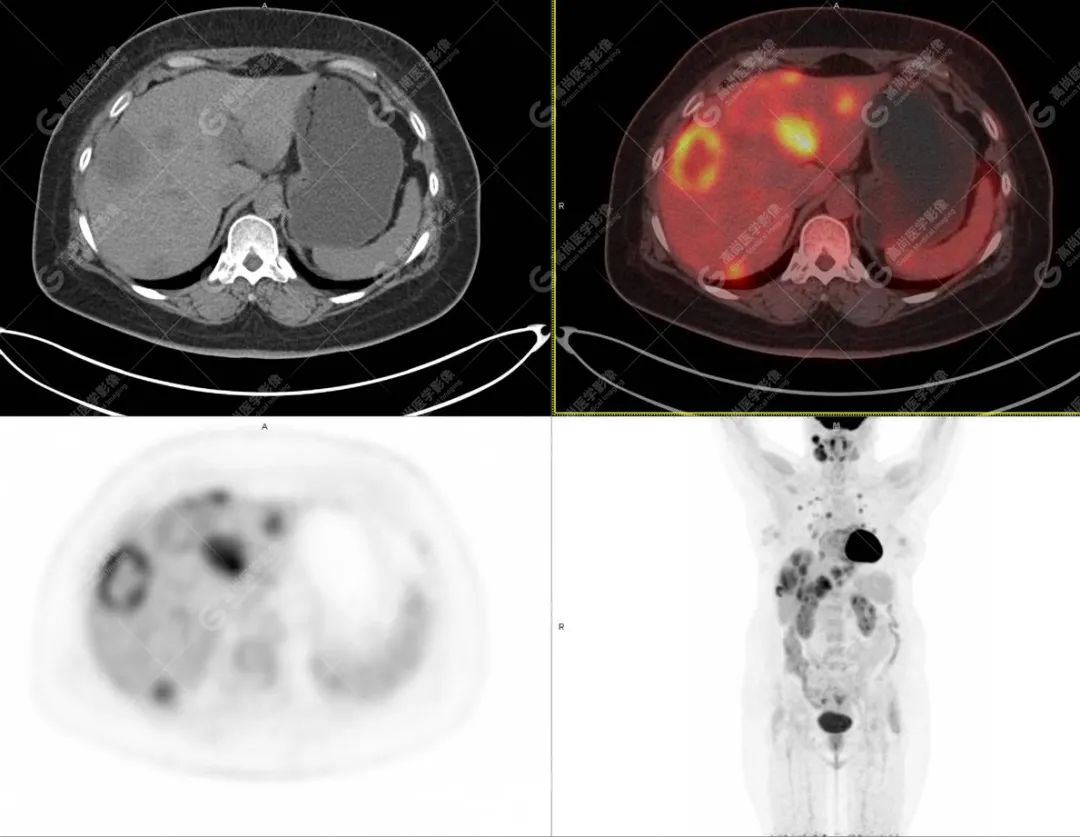

影像诊断:1. 结合病史,右颈部神经鞘瘤(低度恶性)术后改变,右侧颈部稍低密度及等密度结节,代谢异常增高,考虑为肿瘤复发并右颈部淋巴结转移,建议活检。 2. 双侧肺门及纵隔(4R 区)多发肿大淋巴结,代谢异常增高,考虑为转移。 3. 双肺多发大小不等实性结节,部分代谢增高,考虑为转移。 4. 肝脏多发低密度结节及肿块,代谢异常增高,考虑为转移。 5. 右侧第 8 前肋骨骨质破坏,代谢异常增高,考虑为转移。